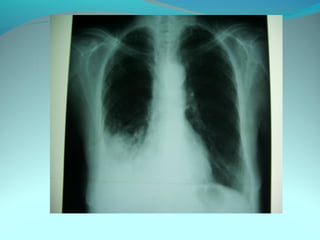

Image radiologique bilatirale a type d’opacité nodulaire occupant les

2/3 sup du poumon droit et la ½ sup du P G confluante par pour

former de grosses opacités

DIAGNOSTIC:

Tuberculose pulmonaire bilateral

Pneumonie bilaterale